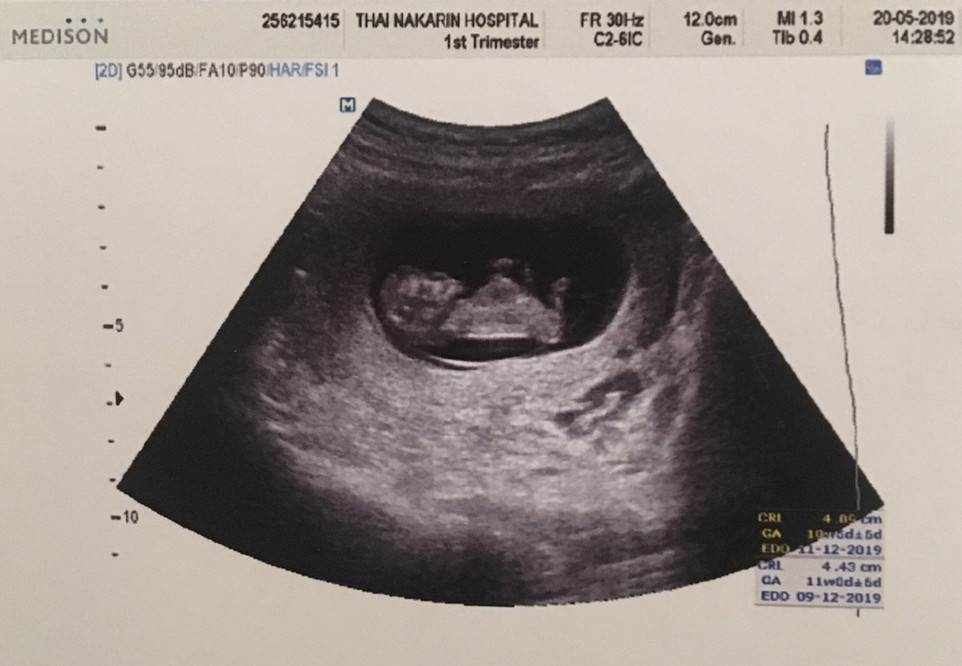

บ้านนี้11w2dค่ะ

มีภาพตอน12w+5d ค่ะ